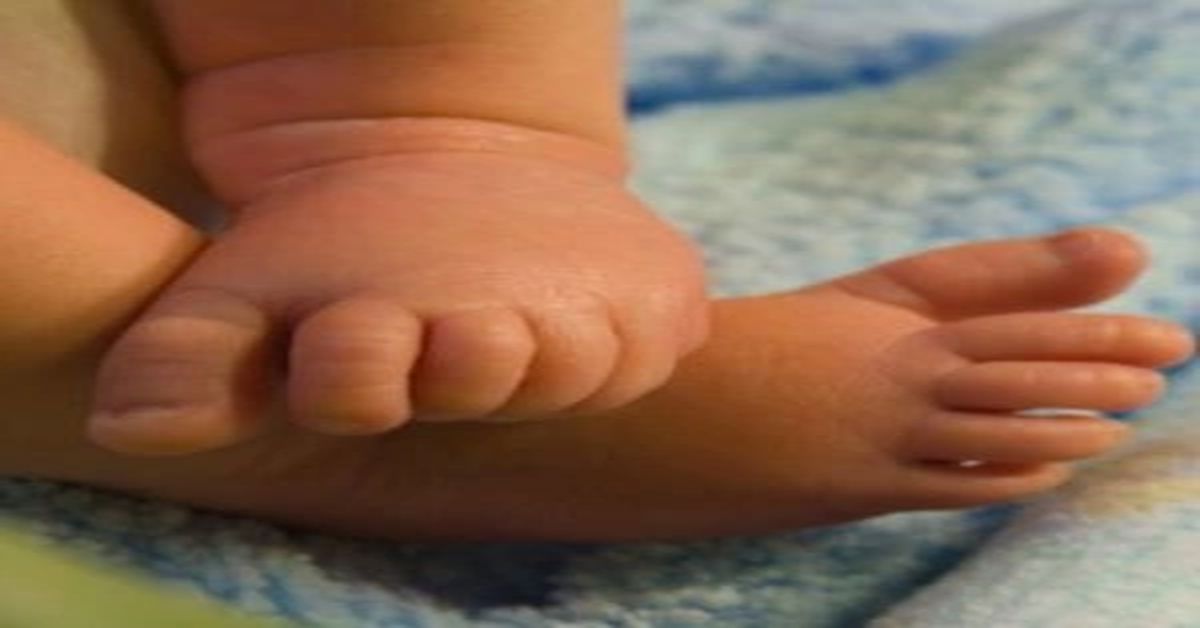

وهو شائع بشكل خاص عند النساء الذين تتراوح أعمارهم بين 40-60 سنة. هذه الحالة هي نتيجة للتغيرات الهرمونية وتغير مرونة الأنسجة مع تقدم العمر. يمكن أن تؤدي إصابات اليد أو الأصابع أيضًا إلى الإصابة بإصبع الزناد. يمكن أن تؤدي الإصابات إلى التهاب وتضييق لاحق في أغلفة الوتر.

قد يكون لدى بعض الأشخاص أغلفة وتر أضيق منذ الولادة. وهذا يجعلها أكثر عرضة للتشكيل. وينجم عن المجموعات المهنية أو الأنشطة التي تجهد اليدين والأصابع بشكل مزمن. في حالة الاستخدام المستمر وإجهاد اليد، يحدث تآكل والتهاب أكثر من المعتاد.